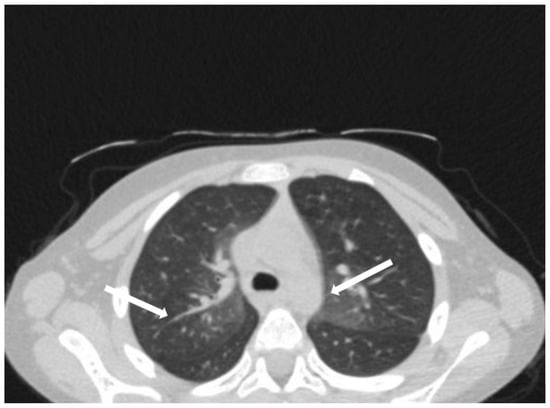

The patient was hospitalized in the Pediatric Clinic I for 3 weeks, being closely monitored (seriated clinical exam, laboratory tests, and echocardiography). The patient’s evolution gradually became favorable, and he was discharged with the recommendation to continue antiplatelet therapy and low-dose oral steroids. However, 4 days after discharge, the patient presented to the Emergency Department with altered general condition, respiratory distress, and fatigue. Laboratory tests revealed leukocytosis (27.720 × 103/μL), with neutrophilia (22.970 × 103/μL), thrombocytosis (491 × 103/μL), monocytosis (2.180 × 103/μL), and elevated inflammatory markers (CRP > 180 mg/L, ESR 43 mm/h), while urine analysis and cardiac enzymes were within normal limits. In the emergency department, a chest X-ray was performed which pointed out diffuse peribronchovascular infiltrates and inferior interclavicular hilar infiltrates (Figure 1). Given the influenced general condition and the presence of respiratory failure (oxygen saturation of 90%), along with the findings of the chest X-ray, we decided also to perform pulmonary computed tomography (CT), which identified ground-glass opacities with subpleural disposition adjacent to the mediastinum, in the upper lobes at the apical and posterior segments of the right lung, and at the apicoposterior segment of the left lung. Additionally, in the lower pulmonary lobes, opacities were observed in the bilateral posterior segments, left anteromedial, and right medial segments, indicative of possible pulmonary hypertension/incipient pulmonary edema/acute respiratory distress syndrome (ARDS) (Figure 2 and Figure 3). Pulmonary hypertension and pulmonary edema were ruled out based on clinical findings, cardiac examination, and normal cardiac enzymes. Based on all these findings, we considered pneumonia in the context of immunosuppression and we performed several tests to identify the possible etiology, finding elevated positive anti-CMV IgM antibodies and increased IgG antibodies of CMV (967.9 U/mL), which were confirmed by subsequent repeated tests. Additionally, we found evidence of hepatocellular injury (ALT: 166 U/L; AST: 60.7 U/L) prompting intravenous hepatoprotective treatment and initiation of an unspecified immunomodulatory agent, inosine acedoben dimepranol, orally, at a dose of 50 mg/kg body weight per day. This approach was chosen due to limitations in specific antiviral therapy for the pediatric population.

Figure 3. In the lower pulmonary lobes, opacities were observed in the bilateral posterior segments: left anteromedial and right medial segments (white arrows).